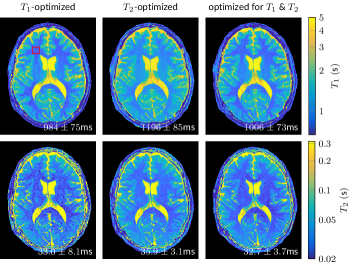

Fig. 5 depicts quantitative in vivo maps acquired with the patterns shown in Fig. 2k,n,q and with one radial k-space spoke acquired for each time frame. The total scan time was approximately 3.83.83.8s for each of the three experiments. Systematic deviations can be noted in the measured relaxation times (Fig. 5). These variations are most likely caused by magnetization transfer 30, which is not addressed in the present work. Focusing on the noise properties, one can observe a good agreement between the Cramér-Rao bound predictions and the resulting noise level in the parameter maps. As anticipated, the purely T1subscript𝑇1T_{1}-optimized pattern and the jointly-optimized pattern achieve a very similar SNR level in the T1subscript𝑇1T_{1}-maps (cf. Fig. 3a), while the T2subscript𝑇2T_{2}-optimized pattern is slightly worse. The gap is substantially larger in the T2subscript𝑇2T_{2}-maps, where the T2subscript𝑇2T_{2}-optimized and the jointly-optimized patterns achieve similar performance, but the T1subscript𝑇1T_{1}-optimized pattern has a substantially larger standard deviation (cf. the ROI analysis displayed in the corner of Fig. 5).

Refer to caption

Figure 5: The in vivo data were acquired with the excitation patterns depicted in Fig. 2j-r with the limit 0ϑπ/40italic-ϑ𝜋40\leq\vartheta\leq\pi/4. The parameter maps have an in-plane resolution of 1mm1mm1~{}\text{mm} and were acquired in 3.8s3.8s3.8\text{s}. Note the logarithmic scale of the T1subscript𝑇1T_{1} and T2subscript𝑇2T_{2} color maps. The red rectangle indicates the region of interest used for calculating the mean and standard deviation denoted in the corner of the images.